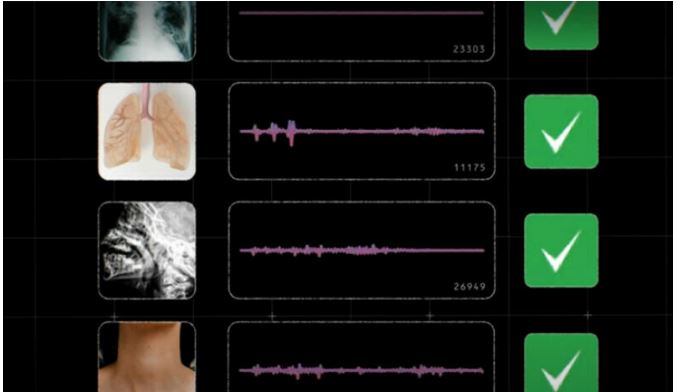

بعد ازاں ماہرین نے مذکورہ آوازوں کو اے آئی ٹولز کے ذریعے جانچا اور آوازوں کے ذریعے ہی لوگوں میں بیماری کی تشخیص کی۔گوگل نے دعوی کیا کہ اے آئی ٹولز کے ذریعے کھانسی اور چھینکنے سمیت بولنے اور سانس لینے کے انداز سے بھی ٹی بی اور پھیپھڑوں کی بیماریوں کی تشخیص ہو سکتی ہے۔

کمپنی کے مطابق گوگل کی جانب سے تیار کردہ اے آئی ٹول کو بھارتی آرٹیفیشل انٹیلی جنس ہیلتھ کمپنی سواسا استعمال کر رہی ہے اور وہ بڑے پیمانے پر ٹی بی اور پھیپھڑوں کی بیماریوں کی تشخیص کر رہی ہے۔مذکورہ اے آئی ٹولز کے ذریعے کسی بھی عام اسمارٹ فون کے ذریعے ایپ سے منسلک ہوکر کھانسنے اور چھینکنے کے بعد بیماری کی تشخیص کی جا سکتی ہے۔